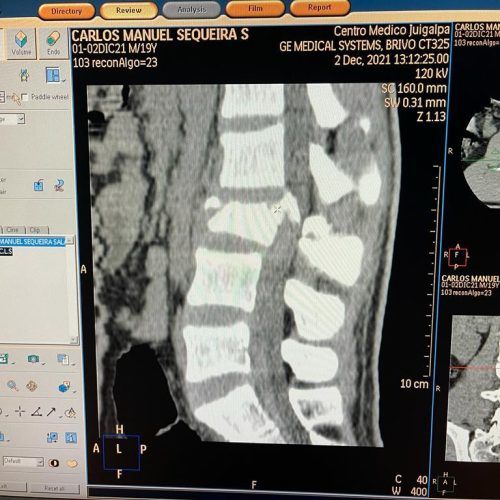

4. Fusión Vertebral (Lumbosacra o Cervical)

¿Qué es?

Cirugía que une dos o más vértebras para estabilizar la columna y aliviar el dolor.

Fusión Vertebral (Cervical o Lumbosacra)

Es un procedimiento quirúrgico que busca estabilizar la columna vertebral uniendo de forma permanente dos o más vértebras. Se utilizan tornillos, barras y, en ocasiones, una caja intersomática con injerto óseo, para que las vértebras se fusionen en una sola unidad sólida.

¿Cuándo se indica?

- Espondilolistesis (desplazamiento vertebral)

- Inestabilidad vertebral causada por degeneración

- Fracturas vertebrales traumáticas

- Enfermedades degenerativas del disco

- Deformidades como escoliosis o cifosis

- Cirugías previas fallidas